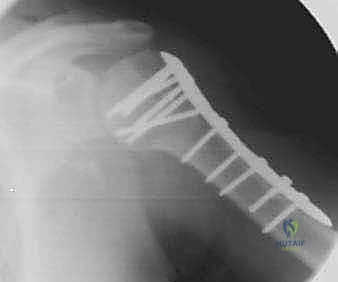

1. الرد المفتوح والتثبيت الداخلي (ORIF - Open Reduction and Internal Fixation)

هذا هو المعيار الذهبي لعلاج معظم الكسور النازحة (جزأين أو ثلاثة أجزاء، وبعض كسور الأربعة أجزاء لدى الشباب). يقوم الدكتور هطيف بفتح الكتف، وإعادة ترتيب الشظايا العظمية بدقة متناهية (الرد المفتوح)، ثم تثبيتها باستخدام شرائح معدنية تشريحية ذاتية القفل (Locking Plates - PHILOS) ومسامير.

* ميزة الشرائح ذاتية القفل: تمنح تثبيتاً قوياً جداً حتى في العظام الضعيفة والمصابة بالهشاشة، مما يسمح للمريض ببدء العلاج الطبيعي في وقت مبكر.